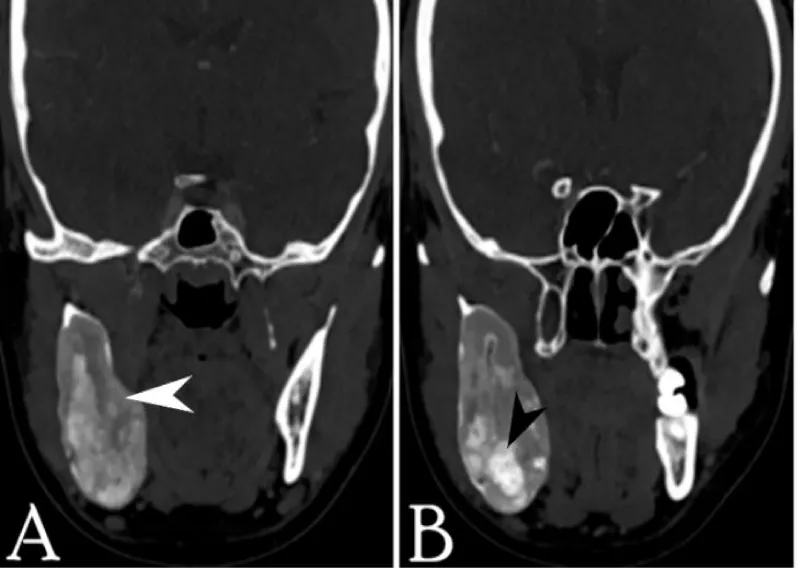

CT scan with contrast was recommended to elicit the extent of the lesion and to characterize the radiological features. It showed a large well corticated, sharply marginated mixed density expansile lesion involving the ramus and body of mandible reaching up to the root of the right lower molar tooth. There was no evidence of cortical break, destruction, or erosion of involved bone. Few intra-lesional hyperdense areas were seen representing calcific foci/ cementing material (Figures 4-6).

In the Radiological aspect, initially, the cemento-ossifying fibroma appears as a well-defined radiolucent lesion with no evidence of internal radio densities. As the tumor progresses, there is evidence of calcification so that the radiolucent area opacifies, and eventually, the lesion appears as a lobulated almost complete radiopaque mass in the mature stage. An important diagnostic feature of cemento-ossifying fibroma is the expansion of lesions equally in all directions and present as a round tumor mass. The cortical plate may be expanded, displaced, thinned out, and remains intact. Teeth adjacent to or involved in the lesion may be displaced but resorption is not associated with this tumor [3,4,6,9]. In our case the tumor was large well corticated, sharply marginated mixed density with high densities representing calcific foci/cementing material, expansile lesion with no evidence of bone destruction or cortical break.